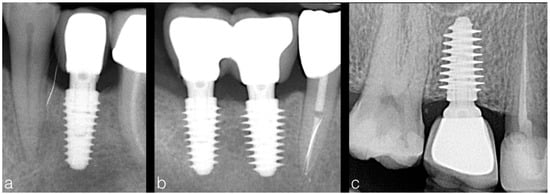

After one year of prosthetic loading, implants were clinically evaluated and an additional periapical x-ray using paralleling long cone technique was performed (Figure 2). Marginal bone level was determined from linear measurements made on DBSWIN software (Version 5.7.1, Dürr Dental, Bietigheim-Bissingen, Germany), by two examiners (blinded to implant stability values) on each periapical radiograph from the most mesial and distal points of the implant platform to the first corresponding point of bone/implant contact, as previously described []. The 1:1 magnification of the x-rays was validated by measuring the known implant length and width.

Figure 2.

One year post-loading periapical radiographs showing implants placed in different bone density with variable thread depth (a—4 mm, b—4.5 and 5 mm, c—5.5 mm). Implants inserted in hard bone presented minimal thread depth (a) to avoid excessive bone compression, while implants with deep threads were used in soft bone (c) in order to attain higher primary stability.